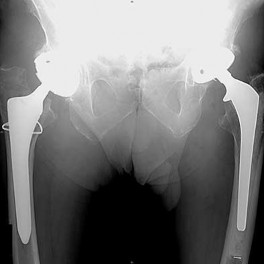

What is the most likely explanation for the change between the initial intraoperative radiograph (Figure 11a) and the radiograph taken 4 weeks after surgery (Figure 11b) in an 87-year-old man who underwent primary hip replacement for osteoarthritis?

The image demonstrates subsidence of the femoral implant. The implant subsided because it did not have good initial stability. The tapered femoral implant was placed after initial preparation for an anatomic femoral stem. A limited, nondisplaced femoral neck fracture was encountered during the procedure and treated. Two advantages of tapered stems are the efficient transfer of stress to the proximal femur and the ability to accommodate some subsidence to achieve enhanced stability. Although subsidence of a tapered stem to a more stable position can produce a good result, quality of metaphyseal bone should be considered. Attention to surgical technique remains important to optimize component stability for biological fixation.